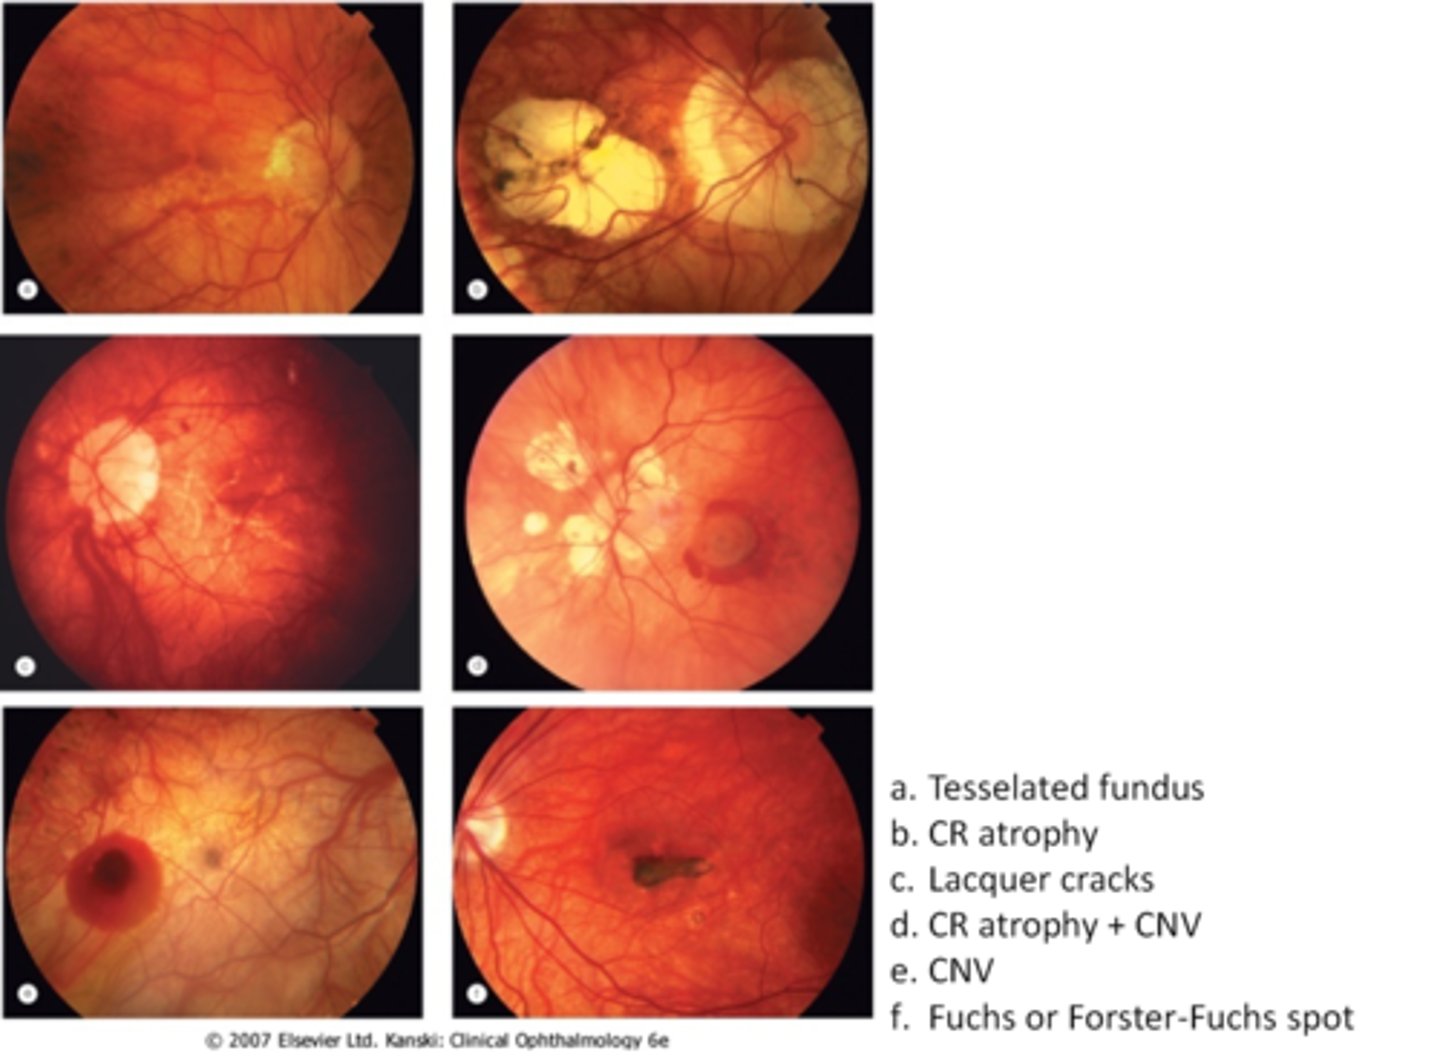

tesselated or tigroid fundus = visibility of choroidal vasculature (A)

What are some common findings in degenerative myopia?

lacquer cracks (C)

CNV (E)

chorioretinal atrophy (B)

What findings of degenerative myopia are seen here?

PPA

crescent

lacquer cracks

How do lacquer cracks appear on fundoscopy?

jagged, irregular yellow lines showing sclera in the posterior pole